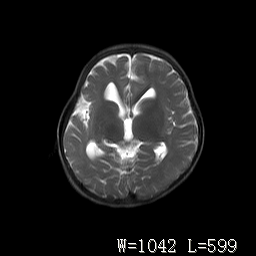

标题: PED3252:脑室增大。

女,3岁,3岁不会说话,阵发性抽搐、自伤。

考虑为梗阻性脑积水(中脑导水管狭窄)。

侧脑室不规则,前后角尖角样,脑白质较少:考虑灰质发育不良可能

倒数第3附图不是这个病人的吧!考虑脑白质发育不良可能。